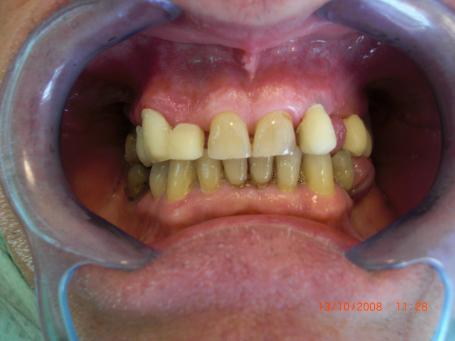

1°)Photo préopératoire initiale.

Homme de 62 ans qui se présente au cabinet dentaire avec une demande de réhabilitation prothétique globale esthétique. Il y a en bouche la présence de nombreuses prothèses iatrogènes inesthétiques. Un examen clinique initiale est réalisé ainsi que le plan de traitement prothétique.